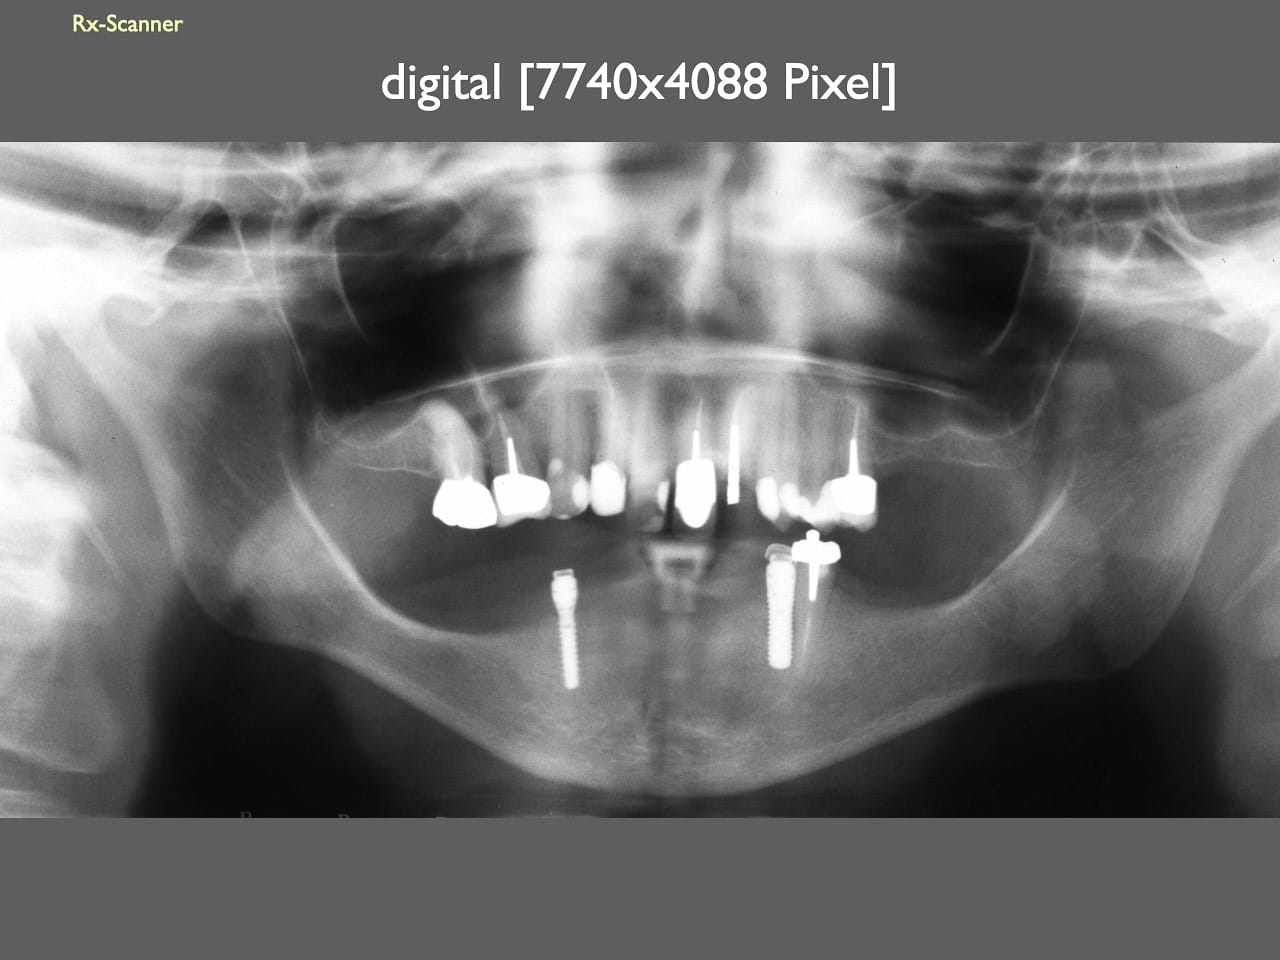

dental Scannen in der Zahnarztpraxis. Study Club vom 28.2.2010. Von peter portmann, Veröffentlicht am 28. Feb. 2010 — 3 min Lesezeit dokumentationfoto Auf dieser Seite Zahnarztpraxis-Trilogie zu Fotografie und Dokumentation Portrait Fotografie Scannen Scannen